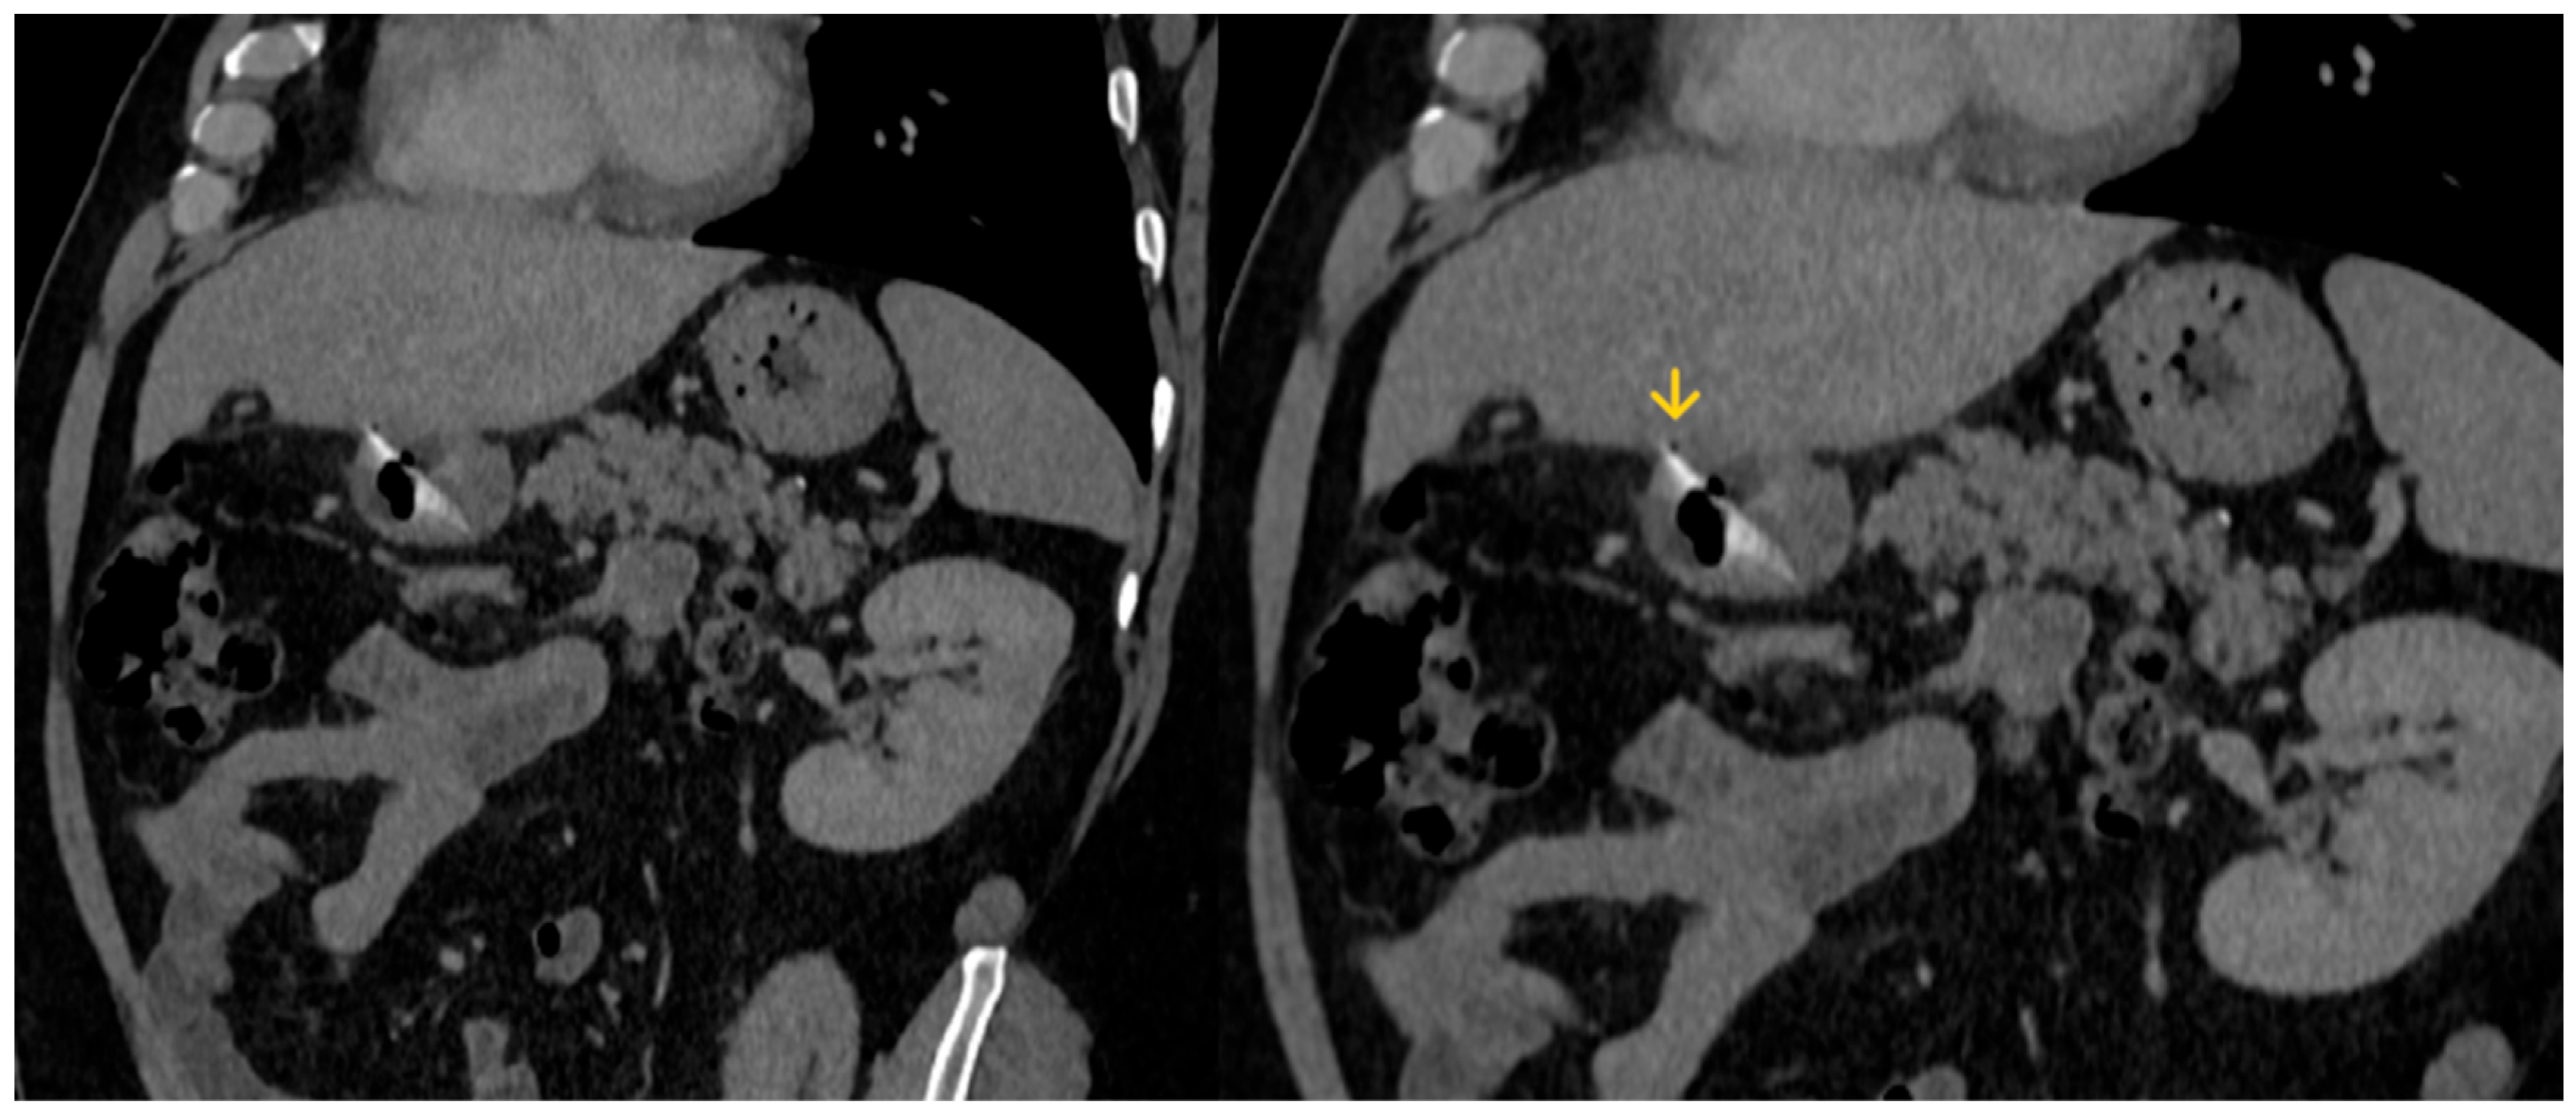

The abdominal CT scan showed a foreign body in the pylorus of the stomach that was penetrating the wall of the stomach (Figure 1). There was also air outside the stomach, along with signs of inflammation in the adjacent adipose fatty tissue (Figure 2 and Figure 3). The diagnosis of perforation of the stomach wall with a foreign body was made, leading to subsequent concealed, local peritonitis.

Figure 3. A small amount of gas (yellow arrow) is depicted outside the stomach wall, due to perforation.